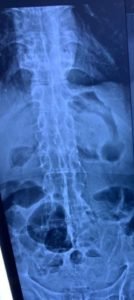

As such Plain X Ray and CT was advised which showed classic bamboo spine and Anderson lesion as shown in

The final diagnosis was Ankylosing spondylitis .